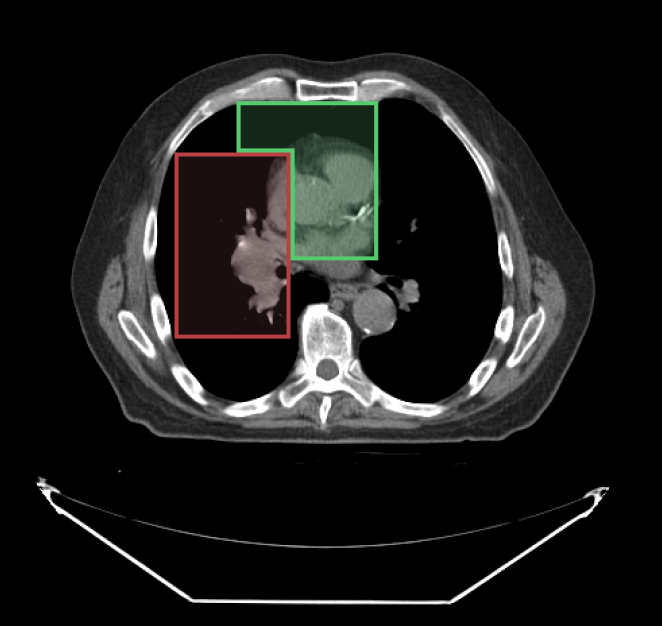

When drawing with segmentation tools, you can specify which segment index to use. Below, we have used the SegmentIndex API to change the segmentIndex to draw the second segment.